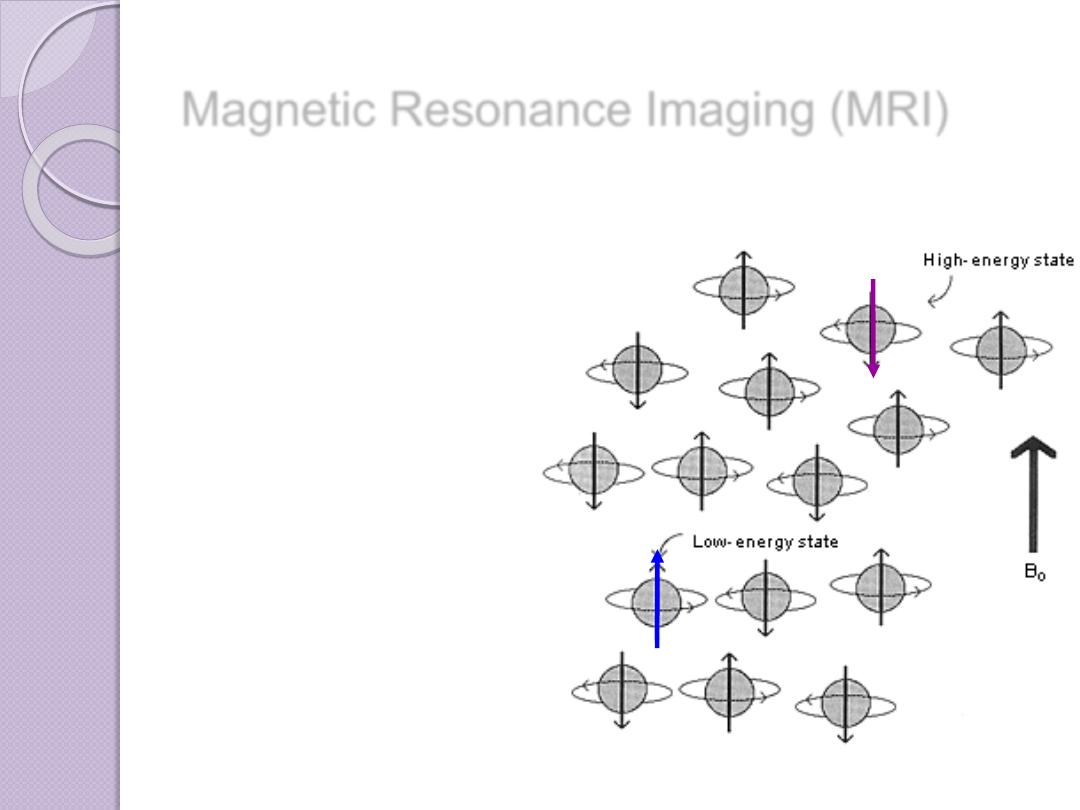

Magnetic Resonance Imaging (MRI)

In the absence of any external forces,

the magnetic moments of protons in

tissue are oriented randomly

Magnetic Resonance Imaging (MRI)

If the protons are placed in a strong

magnetic field, their magnetic dipoles

align

with

and

against

the strong

magnet

Magnetic Resonance Imaging (MRI)

Magnetic resonance imaging (MRI) combines a strong

magnetic field

and

radiofrequency

(RF) energy to study the distribution and behaviour of hydrogen protons

in fat and water

RF energy is used to generate a second magnetic field,

perpendicular to the static magnetic field of the

machine.

The result of this second

magnetic field is to rotate or

flip the protons away from the

static magnetic